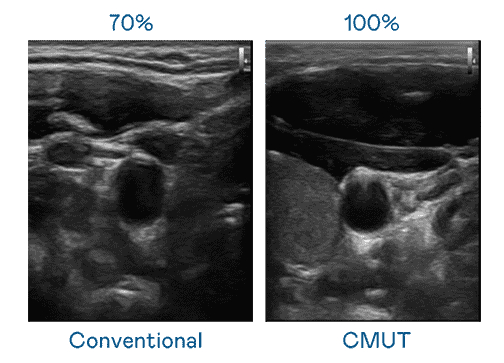

CMUT 技术是一种用电容式微机电元件来产生超音波讯号的技术。。与传统 PZT 压电式技术相比,,CMUT 频宽增加 30%,,,,更宽频的超音波讯号让影像解析度大幅提升,,,,是实现高影像品质医疗超音波扫描、、、、促进精准医疗发展的关键技术。。。

大频宽带来超清晰影像

超音波影像的解析度高低,,,首先取决于探头能发出的讯号频宽。。。尊时凯龙 CMUT 可提供高清晰的超音波讯号,,,,提供高频宽、、、、高灵敏度、、影像纹理细节更高的超音波影像,,,,协助医护人员缩短影像判读时间及利用精准的医疗影像进行诊断。。